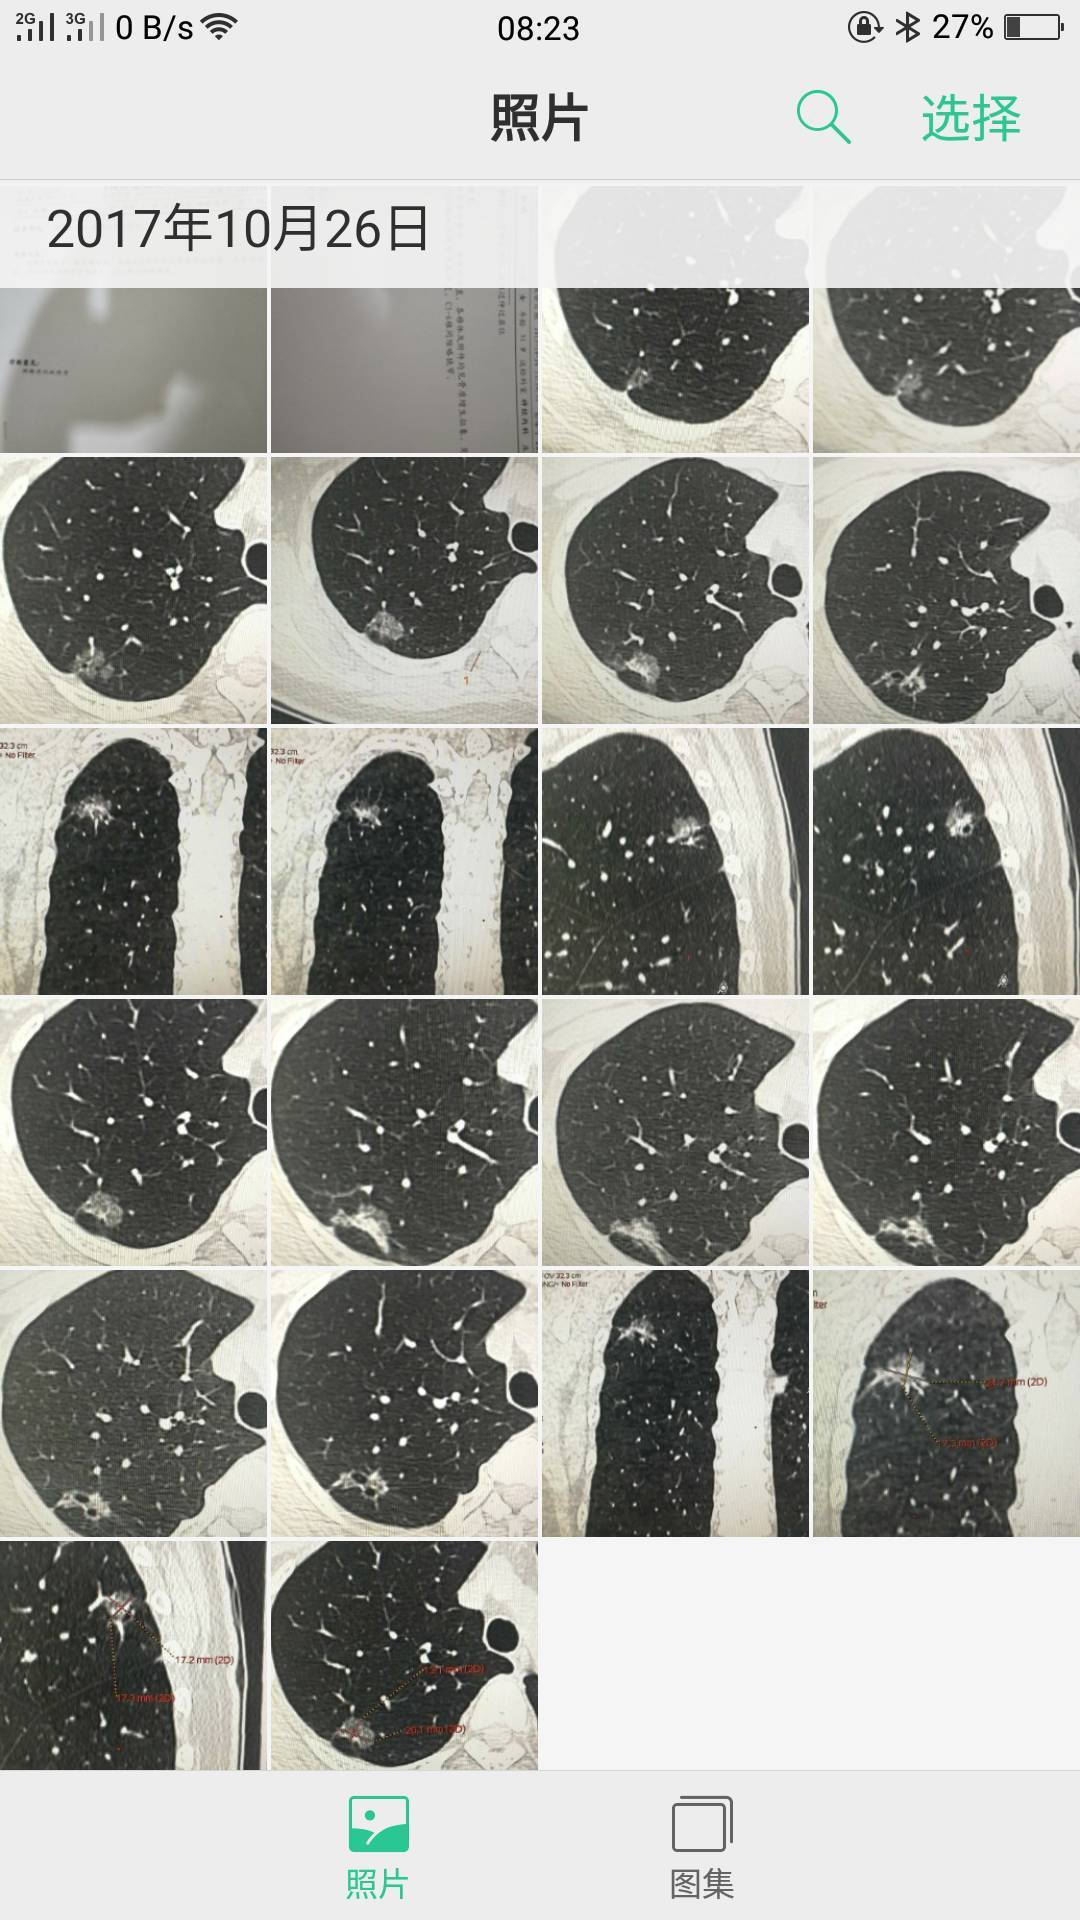

您好,陈大夫,我的图片都是别人从电脑里发给我的,我一点也看不懂哪个是左肺的哪个是右肺的,这就是所有的图了,我这样发给你不知道行不行?谢谢您了,认真负责的好大夫啊!现在这样的大夫少见啊!

这张

这张

陈波医生把左右两边的一起拍一个镜头里,应该还是局限在右上肺的原位癌,但还是想看全肺把其他地方排除一下

陈波医生有时间把CT报告发我看看,你是哪个省的,你这个要找手术做得好的,肺癌治疗这个概念太广了